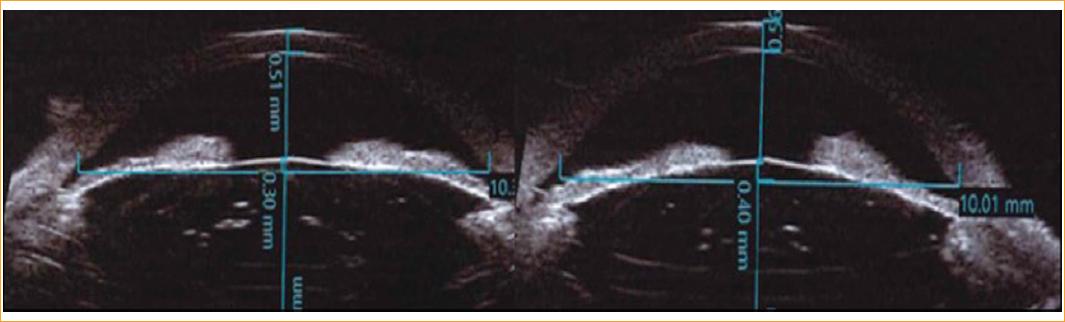

Con el diagnóstico definitivo se decidió realizar iridoplastia periférica con láser argón en ambos ojos (Fig. 3). A las 4 semanas de la iridoplastia, la PIO en el ojo derecho era de 10 mmHg y en el ojo izquierdo de 11 mmHg, con cambios favorables en ambas gonioscopias con ángulos SHAFFER IV en los cuatro cuadrantes de ambos ojos (Fig. 4). Cabe mencionar que desde la primera evaluación se indicó a la paciente apego al tratamiento de timolol/brimonidina 0.5%/0.2%, 1 gota cada 12 horas en ambos ojos.

Es importante mencionar que el diagnóstico de certeza de iris plateau se obtiene mediante UBM, con la cual se observan las características clásicas de este, como son la ausencia del surco ciliar, la presencia de procesos ciliares situados anteriormente que empujan la periferia del iris y la presencia de doble joroba1,2. Así mismo, la UBM permite valorar el eje anteroposterior del cristalino, ya que al estar aumentado puede generar de manera secundaria el empuje de la raíz del iris anteriormente y causar un cierre angular. En nuestra paciente no encontramos dicha característica, pues su eje anteroposterior estaba dentro de parámetros normales (3-6 mm): el ojo derecho con 4.17 mm y el ojo izquierdo con 4.37 mm7. Por ende, no existía ese efecto de empuje del cristalino, y además nuestra paciente no presentó una opacidad del cristalino lo suficientemente densa como para considerar la cirugía de catarata. Retirar un cristalino claro en casos de iris plateau es un tema de gran controversia por el riesgo quirúrgico inherente a la cirugía de catarata.